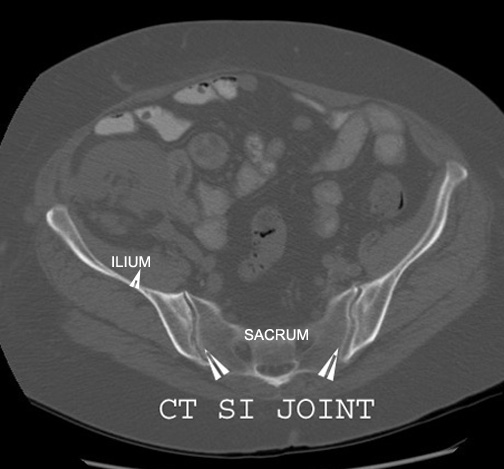

Identify the sacroiliac joint. Click the image for labeling.